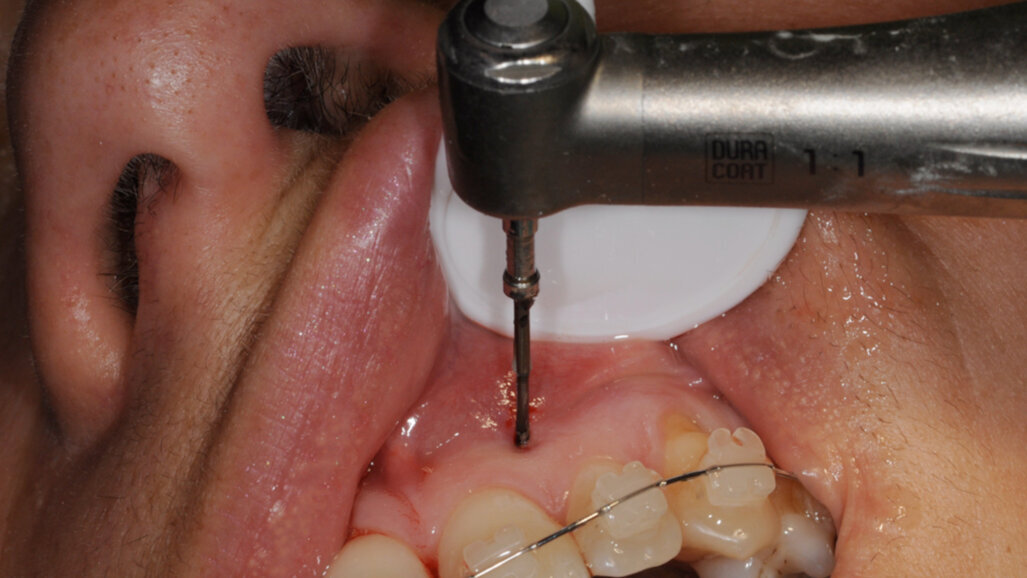

Il s’agit à présent d’instruments manuels et rotatifs. Ils sont réalisés en acier inox recouvert d’une couche de carbone diamant, et présentent une pointe très effilée afin de pénétrer l’os facilement.

L’énorme avantage des ostéotenseurs est le fait de pouvoir les utiliser à ciel fermé, ce qui évite de devoir lever un lambeau mucopériosté, et donc de priver la corticale osseuse de son irrigation.

On commencera ensuite à tester avec les instruments manuels la densité de la corticale osseuse.

Si la densité est faible et que la corticale est aisément passée, on n’utilisera que les instruments manuels. Au contraire face à une corticale dure ou à un os dense, on utilisera les instruments rotatifs sur CA à 20 000 t/min sous irrigation. Pour ces instruments rotatifs, il faut disposer sur l’instrument une butée active, afin d’éviter de léser des structures anatomiques comme le nerf dentaire inférieur.